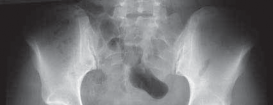

10.

A properly centered anteroposterior pelvis radiograph is essential for assessing the morphology of the hip and comparing the affected to the unaffected side ( FIG 3).

### FIG 3 • An AP radiograph allows comparison of the affected and unaffected hips as well as an assessment of the surrounding bony architecture. It must be properly centered without rotation to assess the radiographic indices of hip morphology accurately. (Courtesy of J. W. Thomas Byrd, MD.) as a cautious indicator in counseling patients on the role of arthoscopy.